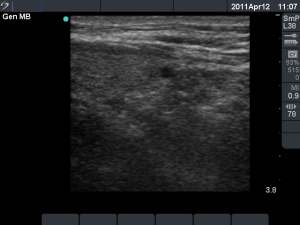

First session (first row of images):

Clinical presentation: the patient told us that her persistent cough lasting for several month have stopped after removal of cystic fluid for five or six weeks. Thereafter this complaint recurred.

Palpation: no abnormality.

Ultrasonography: the cysts has recurred.

We offered ethanol sclerotherapy. We aspirated 4 mL watery fluid and administered 1.5 mL ethanol.